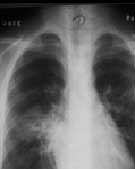

自发病以来多次行胸片和胸部CT检查,变化较大,见附图。

X线胸片1: 入院时(病程2个月时)胸片(右肺门外及左下肺心缘旁可见片影,左上肺纹理乱,右肺门著明,心影丰满) X线胸片

任甄华 主治医师(放射科):X线胸片对于提示肺栓塞有重要参考价值,单纯肺栓塞胸片可能有五种表现:(1)缺血性改变:局部血管纹理减少,即Westermark征;(2)肺血管大小的改变;(3)心脏变化;(4)肺体积缩小;(5)胸膜渗出。值得强调的是,感染性心内膜炎引起的肺栓塞影像学改变与其他病因引起者不同,典型表现为散在、双侧的外周结节与不同程度的肺空洞性损害,损害呈圆形或楔形,多发生在下肺的外侧部分。本病例就体现了这一特点(见附图),这可能与栓子较小且携带病原菌,造成栓塞部位的继发感染有关。

但必须指出,肺栓塞的X线胸片表现多种多样,呈典型锥形改变的非常少见,部分肺栓塞的胸片可看不见任何异常表现。相当一部分胸片呈肺浸润表现,与肺炎相似。可从以下两点加以区别:①肺部一侧病变吸收,而另一侧出现新阴影的多发病变;②片影吸收呈“溶化征”,而肺炎吸收中片影出现密度不均现象,由此可见,在诊断中胸片的动态观察更为重要。有以上表现者应高度怀疑肺栓塞,再结合患儿是否存在高危因素,临床可做出正确诊断。切勿仅凭胸片轻易排除肺栓塞。本例患儿存在感染性心内膜炎、三尖瓣赘生物的基础病变,2个月病程中肺部阴影变化了3次,每次均为原有病灶吸收,在不同部位又出现了新的浸润影,结合临床表现,肺栓塞可确诊。